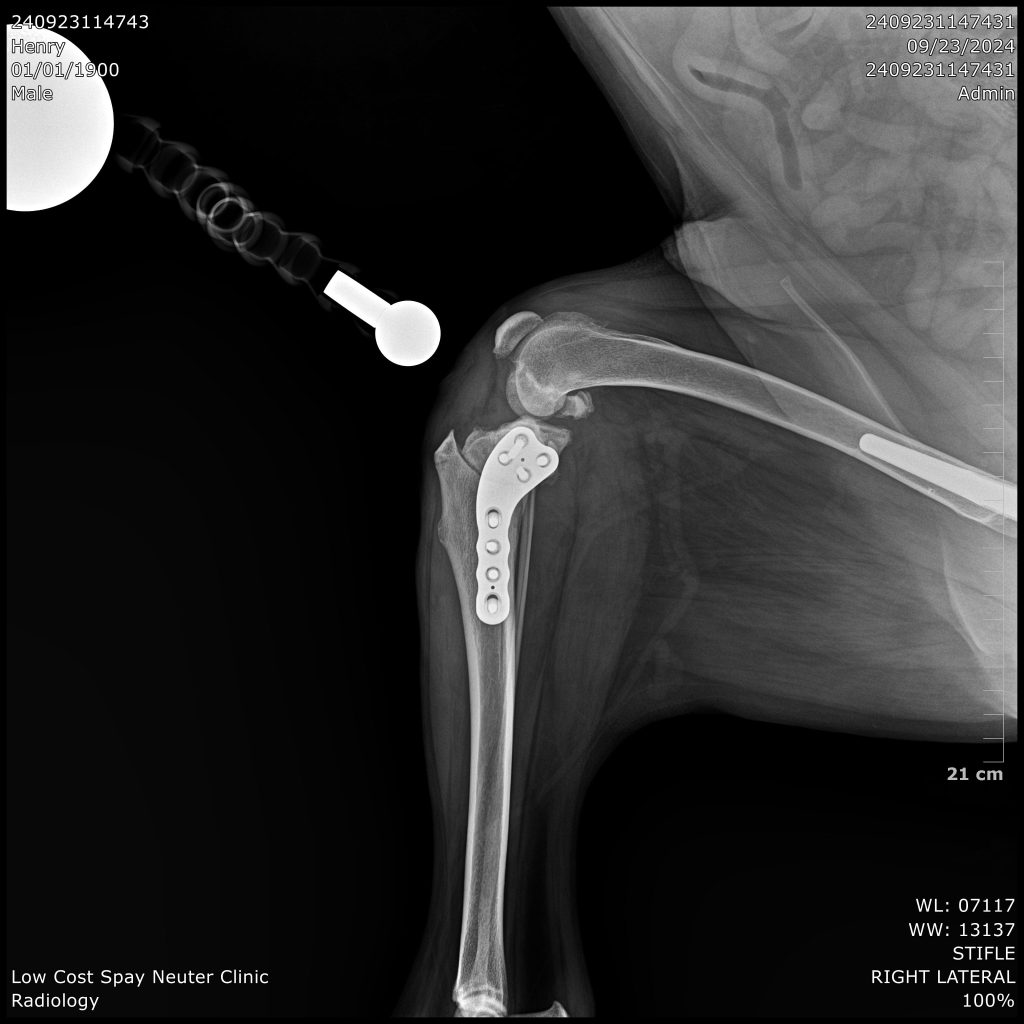

Cranial Cruciate Ligament; (CCL) is one of the most important stabilizers of the knee. It prevents hyperextension, limits internal rotation, and prevents the tibia (shin bone) from sliding forward each time the leg bears weight. When the CCL is damaged, the result is an unstable knee. This instability results in pain and inflammation. Over time, debilitating arthritis develops. Rupture of the cranial cruciate ligament (CCL) of the stifle joint (=knee) is one of the most common orthopedic injury in dogs. It may happen acutely as the result of a true traumatic injury or slow deterioration of the ligament as a dog ages.

TPLO (Tibial Plateau Leveling Osteotomy) surgery stabilizes a dog’s knee joint by altering the angle of the tibial plateau (the top of the shinbone), effectively neutralizing the forces that cause instability when the CCL is damaged. Instead of attempting to repair the torn ligament, TPLO stabilizes the joint by changing the way the femur (thigh bone) and tibia interact during weight-bearing, eliminating the need for a functional CCL.

Price Range $1,200-$3,000